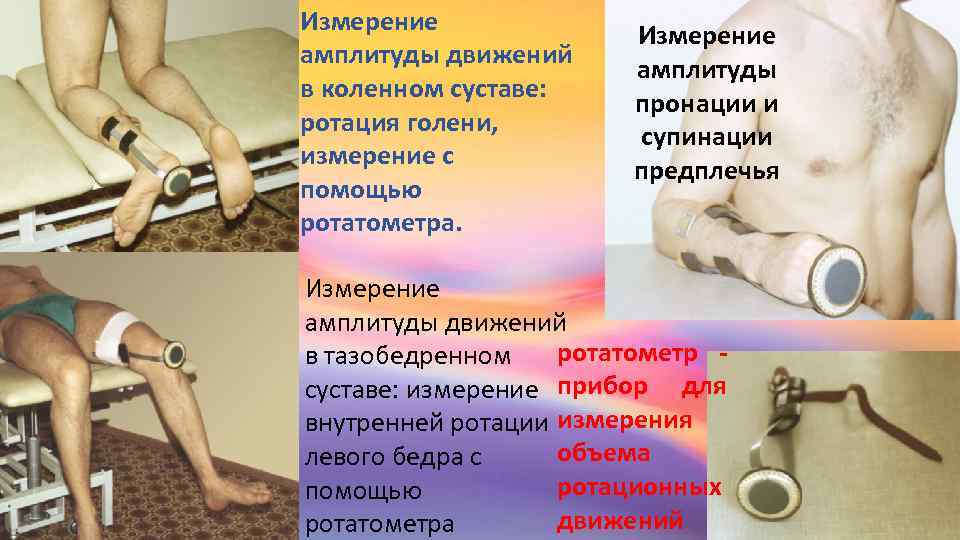

Раздел: Фотозарисовки